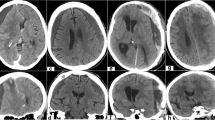

Surgical techniques available for evacuation of acute SDH include craniotomy, decompressive craniectomy, burr hole trephination, or craniostomy procedures [8]. The choice of procedure is influenced by the treating surgeon and the individual patient. The most commonly applied techniques for acute SDH are craniotomy and decompressive craniectomy, with or without duraplasty. Surgical evacuation of acute SDH is performed in a fully staffed operating room, with sterile technique, and under general anesthesia. Given that most SDH undergoing surgical treatment are fronto-parietal or hemispheric in distribution, a large frontal-temporal-parietal craniotomy is usually performed with special attention to the frontal and temporal poles. The craniotomy is started over the temporal lobe, which allows for immediate hematoma evacuation and brainstem decompression. Once the craniotomy is completed, the dura is opened widely. The hematoma is then removed with irrigation, suction, and forceps [85]. Usually, a torn bridging vein or a cortical contusion can be identified and then controlled with bipolar cautery and/or hemostatic agents. Figure 1 shows an example of a frontotemporal craniotomy. If a dural sinus injury is suspected, the anesthesiologist should be alerted to the possibility of significant blood loss as well as the need to monitor for air embolism. While a subdural drain may be left in situ in the setting of coagulopathy or active oozing, primary hemostasis must be obtained in order to prevent reaccumulation of the hematoma. When the brain is relaxed and sunken away from the craniotomy site, a water-tight dural closure is performed and the bone flap is replaced. However, if there is significant edema, or if there is concern for future swelling, the initial craniotomy may be left open or even be extended to allow for adequate decompression. In presence of significant amount of cerebral edema, the dura is only loosely approximated and the scalp flap is closed. The bone flap is stored sterilely in the bone bank and replaced at a later date [85].